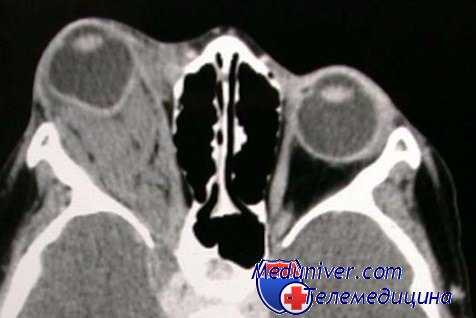

- КТ, МРТ при идиопатическом воспалении глазницы (псевдотуморе)